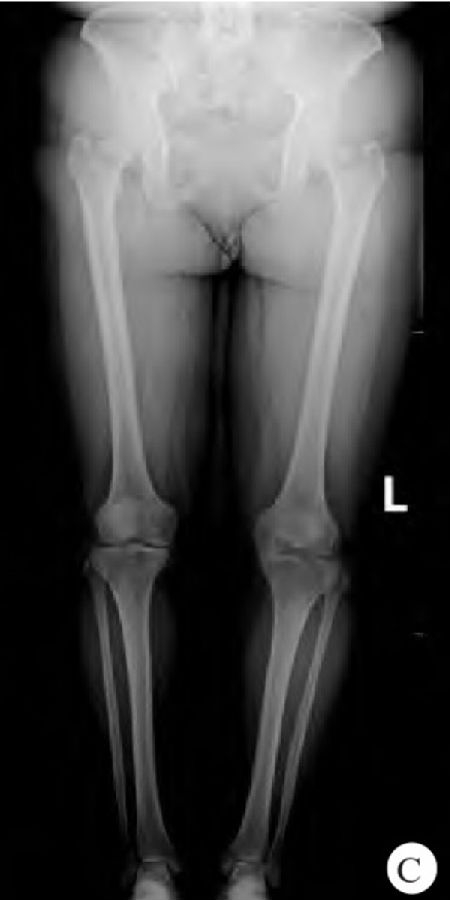

先进行右膝关节内侧UKA,1周后进行左膝关节内侧UKA,其中左膝关节内侧UKA术中内侧副韧带损伤。患者取仰卧位,左下肢屈曲90°。取左膝前髌内侧纵行手术切口长约8cm,依次切开皮肤及皮下组织,切开关节囊,见关节腔少量积液。切除部分脂肪垫,探查见左膝内侧半月板退变明显,股骨内髁及内侧平台软骨面Ⅳ度损伤,前后交叉韧带完整,外侧关节面正常。去除股骨内侧髁及内侧胫骨平台骨赘,切除部分内侧半月板,继续安放胫骨截骨板及截骨力线杆。行胫骨截骨约6mm,后倾5°,完整取出内侧平台骨块。对比试模确认胫骨假体大小为B号胫骨假体。试模满意后,进行股骨内髁试模(为小号)及定位。定位满意后,进行股骨内髁钻孔及去除股骨内髁试模关节面,彻底切除内侧半月板。再次安放股骨及胫骨试模,测量屈伸间隙时发现屈曲及伸直间隙明显增大,8mm衬垫试模仍不稳定。探查内侧副韧带发现近止点处横断损伤,并有部分缺失。考虑切除内侧半月板时同时切除了少量内侧副韧带(图2),直接缝合张力过大,缝合困难。遂用一枚带线锚钉加强缝合内侧副韧带。再次用5mm衬垫试模,膝关节稳定无撞击。取出试模,聚维酮碘、生理盐水反复冲洗,擦干后,用骨水泥固定假体。屈曲膝关节45°,保持骨水泥固化。清除多余骨水泥,待骨水泥完全固化后,为保证膝关节稳定性,安放6mm单髁半月板衬垫。再次测屈伸间隙及屈伸活动正常,膝关节稳定无撞击,X线透视见假体位置合适。放置引流管一根,屈膝位逐层缝合切口,加压包扎切口。气压止血带放气。并给予患者支具固定。术中出血约60mL,手术历时约90min,术后安全返回病房。

图2 术中损伤的内侧副韧带(箭头所示)